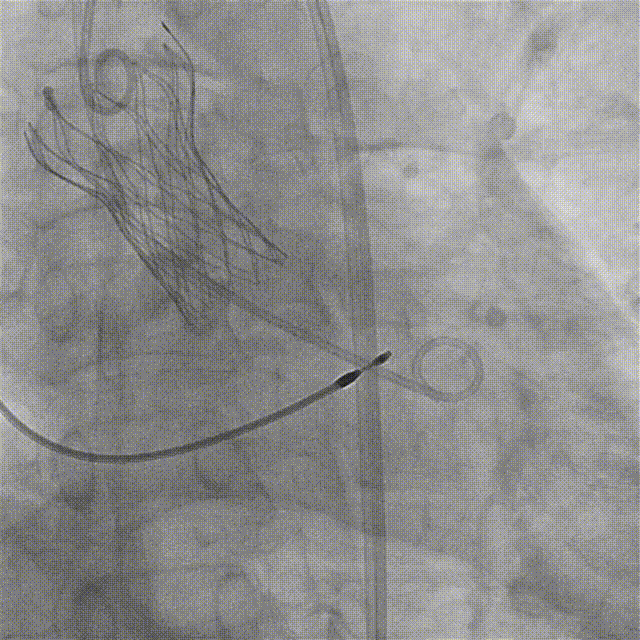

边打造影剂边缓慢撤20F沛嘉大鞘,发现血管夹层

沿导丝送入10mm×100mm覆膜支架至左髂动脉-股总动脉

复查下肢造影显示右髂总动脉-右股总动脉明显狭窄

更换V18导丝后再次送入6.5×60mm赛禾外周冲击波球囊,充盈至4atm下进行一个周期的脉冲治疗

复查右侧髂总动脉-股总动脉造影较前狭窄明显减轻

选择J头导丝带JR4.0造影管翻山选择性造影左侧髂总动脉-股总动脉未见明显狭窄及夹层